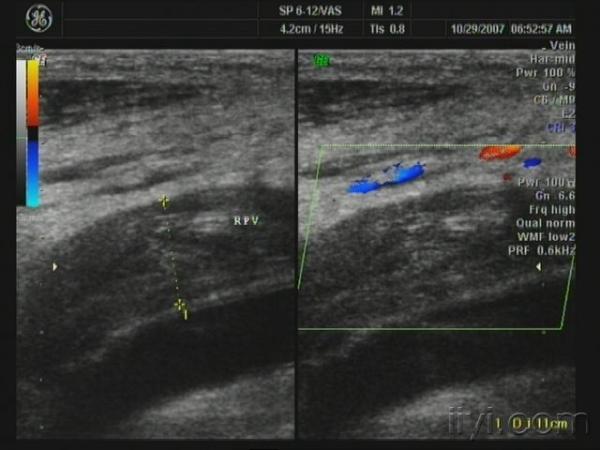

胫后静脉栓塞 - 超声医学讨论版 - 爱爱医医学论坛

一位63的老人因右小腿肿胀疼痛行走不便来医院超声检查的图像,股静脉